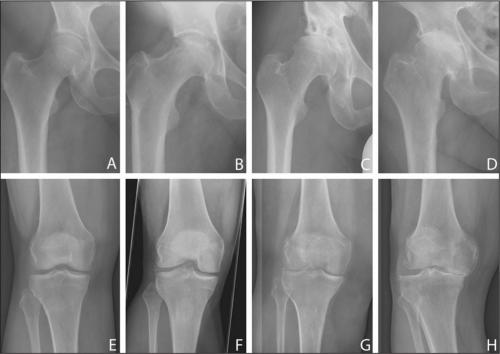

Шкала артрозов — от полного отсутствия болезни до последней стадии. Обратите внимание, как уменьшается суставная щель.